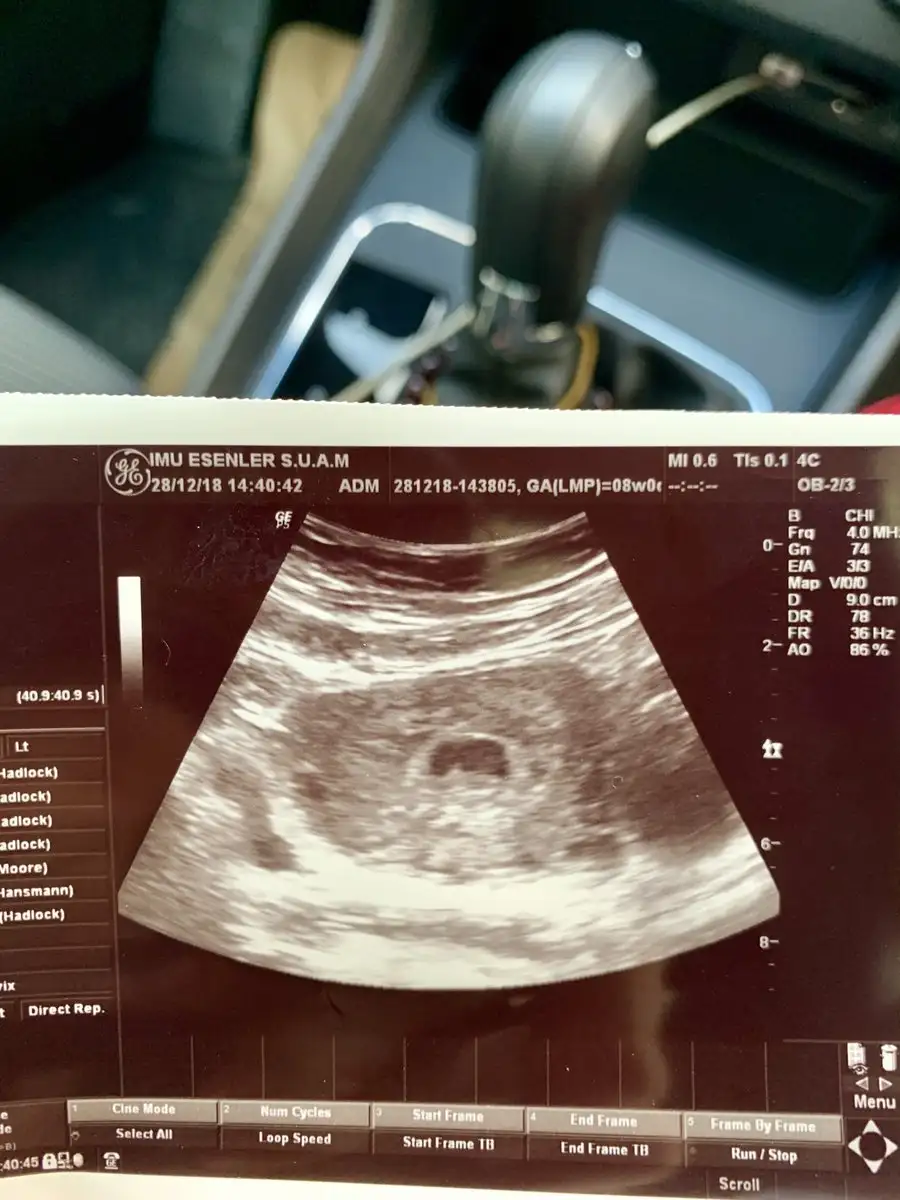

Canim buyuk olan kesede bebegi gorduk ve kalp atislarini duyduk buyuk olan kese 6 haftalik diger kese 1 hafta sonra cikti bizde belki onda da bebegi haftaya gorebiliriz ama gelisemeyedebilir dedi insallah ikiz olarak devam edebiliriz